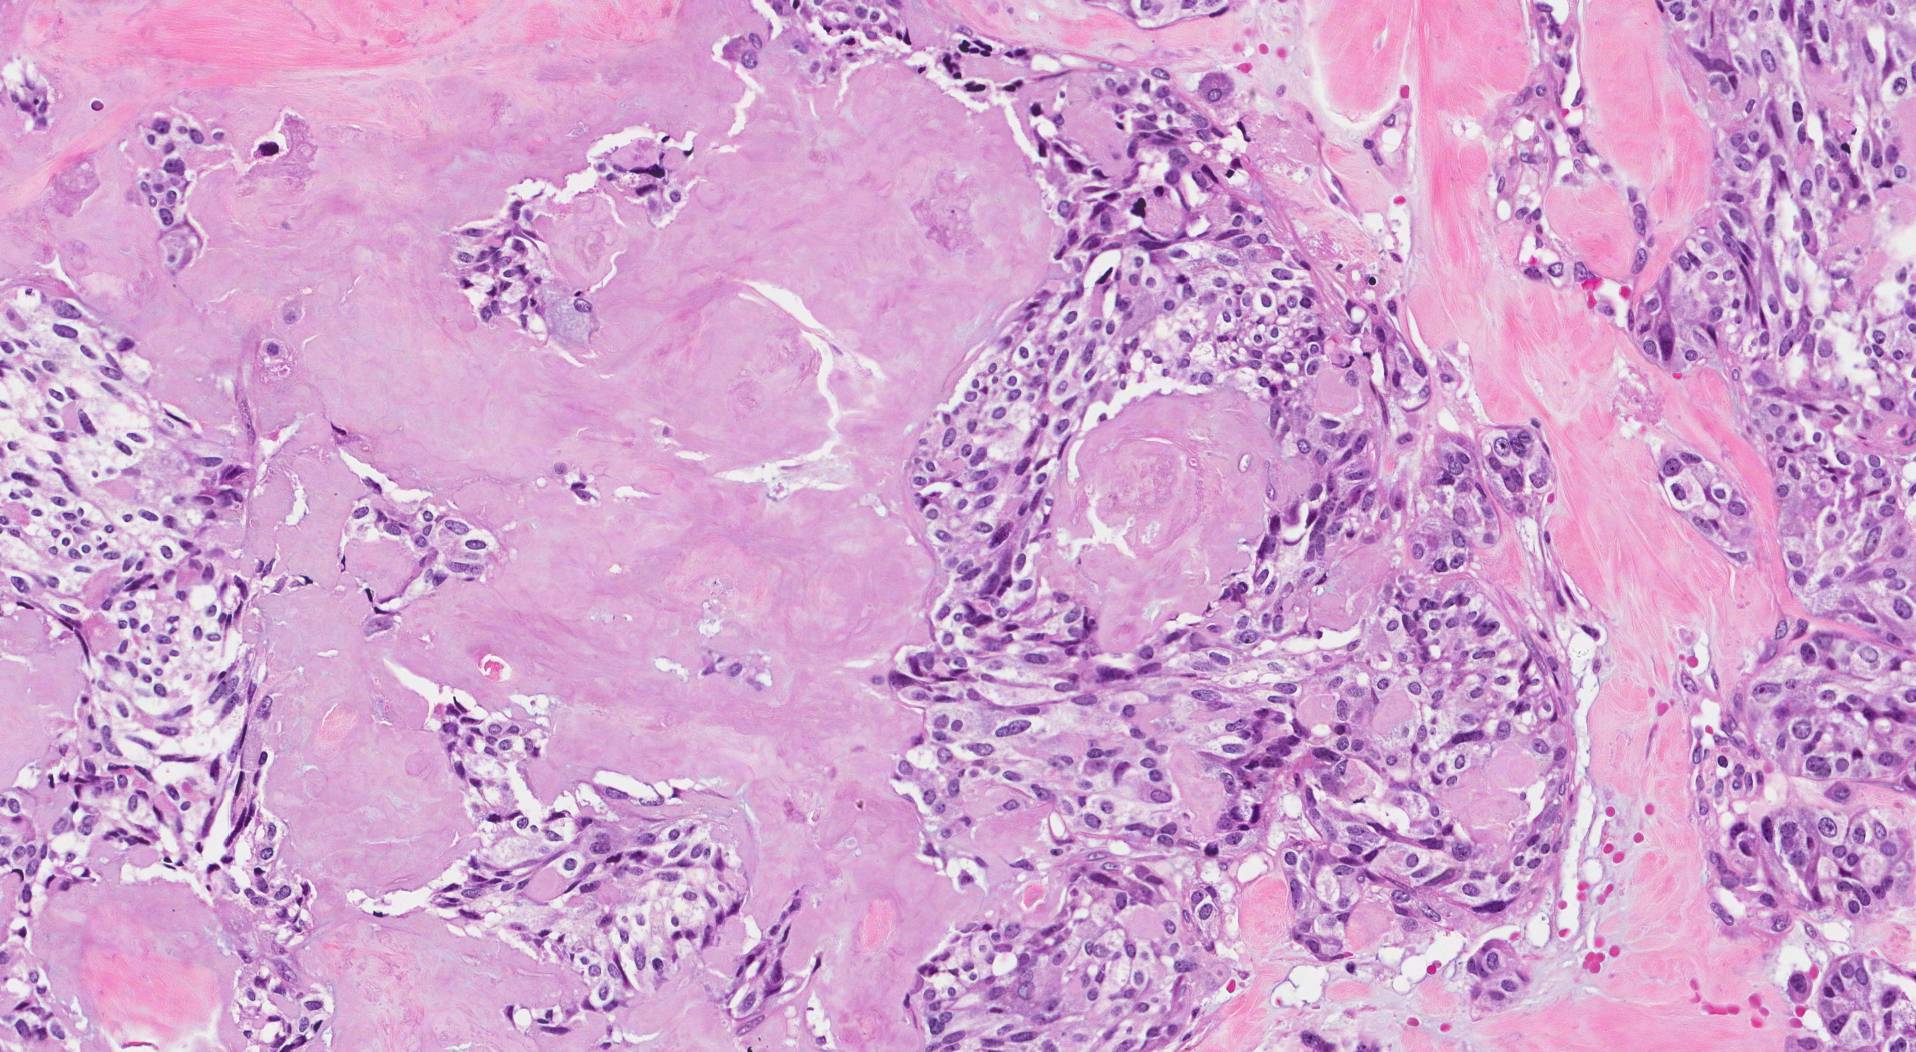

Транстиретиновый амилоидоз с кардиомиопатией (ATTR-кардиомиопатия) является тяжелым прогрессирующим заболеванием, часто приводящим к летальному исходу. При этом заболевании аномальная форма сывороточного белка транстиретина накапливается в виде амилоидных фибрилл в миокарде, что нарушает его сократительную способность и вызывает сердечную недостаточность. На протяжении длительного времени не существовало эффективных методов лечения, однако в последние годы появились подходы, направленные на стабилизацию тетрамерной формы транстиретина и подавление его мРНК. Эти методы показывают клиническую эффективность, но не всем пациентам они помогают и требуют пожизненного назначения.